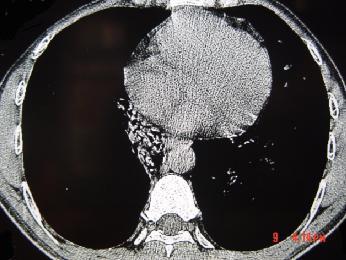

问题 男,26岁,肺部感染后反复咳嗽咳痰一月,CT检查如图,最可能的诊断为 ( )

选项 A、支气管扩张并感染 B、肺癌 C、右下肺隔离症并感染 D、肺部感染 E、支气管囊肿并感染

答案 C